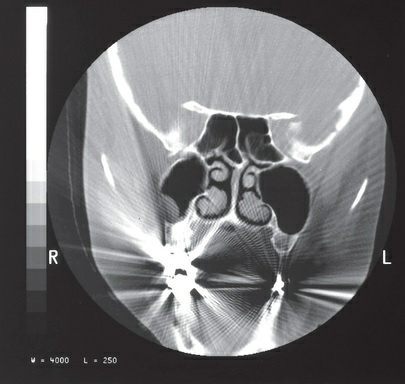

Which of the following is the common term for the artifact

present on the image in the figure?

a. aliasing

b. streaking

c. edge gradient

d. tube arcing

streaking

Which of the following would be the most common cause of

the artifact in the figure?

a. metallic dental fillings

b. partial volume averaging

c. beam hardening

d. detector malfunction

metallic dental fillings

Reduction of the type of artifact seen in the figure on a coronal

multidetector CT (MDCT) view of the sinuses may be

accomplished through:

a. an increase in the mA

b. a decrease in the kVp

c. coronal multiplanar reformation (MPR) images built from an

axial acquisition

d. a reduction in the scan field of view (SFOV)

coronal multiplanar reformation (MPR) images built from an